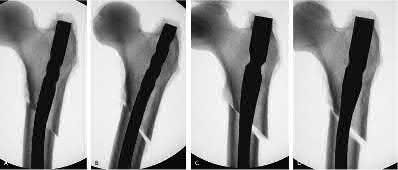

Figure A exhibits ideal starting point for a trochanteric entry nail (B), for a piriformis start nail (C) and a start point that is too lateral, causing varus (A). Illustration A depicts 4 different types of trochanteric entry nails that started at the tip of the greater trochanter and although mostly neutral, still exhibit slight varus.